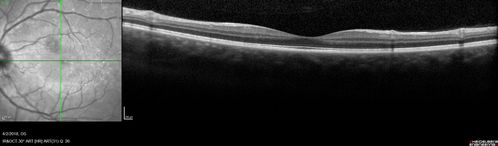

Cat Scratch - Neuroretinitis OD AND retinitis OS - Bartonella henselae positive

27 year old female with exposure to cats and prior fever.  Reports with recent vision loss right eye.  She was treated with doxycycline and within 2 weeks the right eye looks better.  Then she skipped all follow-up visits.  The right eye presented 20/200 and the left 20/16